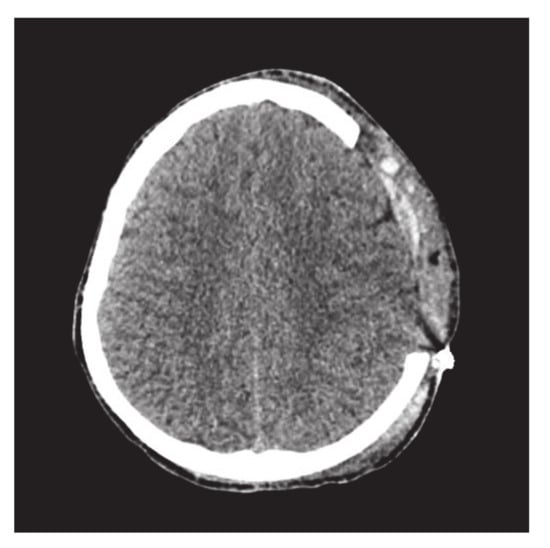

This subsection addresses the critical analysis of different schemes based on Bézier-like functions such as G C 2 , G C 1 , C 1 rational cubic Ball curves, NURBS curves and B-spline curve of degree three. Different types of fractures have been constructed using CT scan, such as in Figure 10. Initially, the C 1 rational cubic Ball curve is used to construct the boundary curve of the fractured part, as shown in Figure 11. This scheme works well for small fractures but it reduces the smoothness and flexibility when the defected part become bigger and irregular, as shown in Figure 12 and Figure 13. However, the results obtained by G C 1 , G C 2 rational cubic Ball curves are better, smoother and more flexible than the C 1 rational cubic Ball curve due to the presence of more shape parameters, as shown in Figure 14. The comparison of all curves is shown in Figure 15. In this figure, the red curve is obtained using the G C 1 rational Ball, the blue and green curves are obtained using the C 1 rational Ball.

Figure 10. Parietal bone fracture.